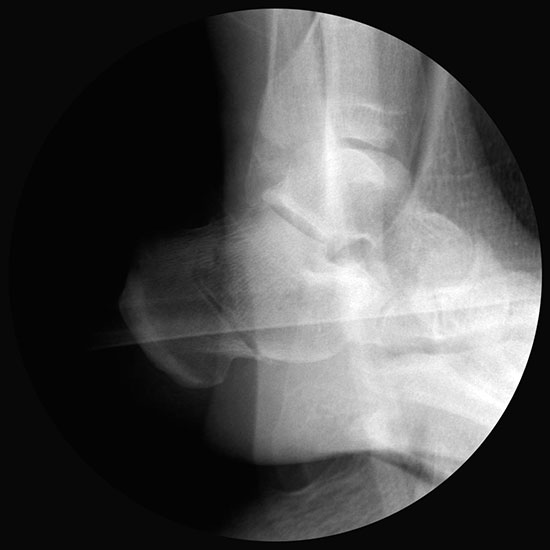

Röntgenaufnahmen des Fußes d.p., streng seitlich und schräg unter Belastung. Saltzmann Aufnahme zur Beurteilung der Rückfussachse.

Operationsplanung anhand der Röntgenaufnahmen unter Beachtung wichtiger radiologischer Landmarks wie Rückfussachse, Metatarsale I – Talushals-Achse im dp und lateralen Strahlengang (Abbildung 1 und 2).

Abbildung 1

Abbildung 2